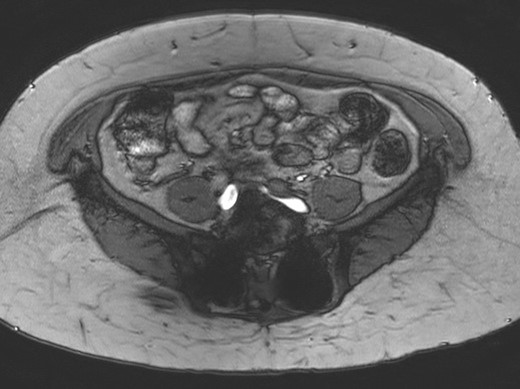

Vascular ultrasound of her left leg showed venous insufficiency in the small saphenous and Giacomini veins. Those findings were not severe enough to cause the level of discomfort that she was experiencing, so magnetic resonance angiography (MRA) of the pelvis was ordered. This study showed narrowing of the left common iliac vein to 0.2 cm (Fig. 1), with a tortuous right common iliac artery crossing over the constriction. The findings were consistent with non-thrombotic May–Thurner syndrome, which was thought to be the cause of her new symptoms.